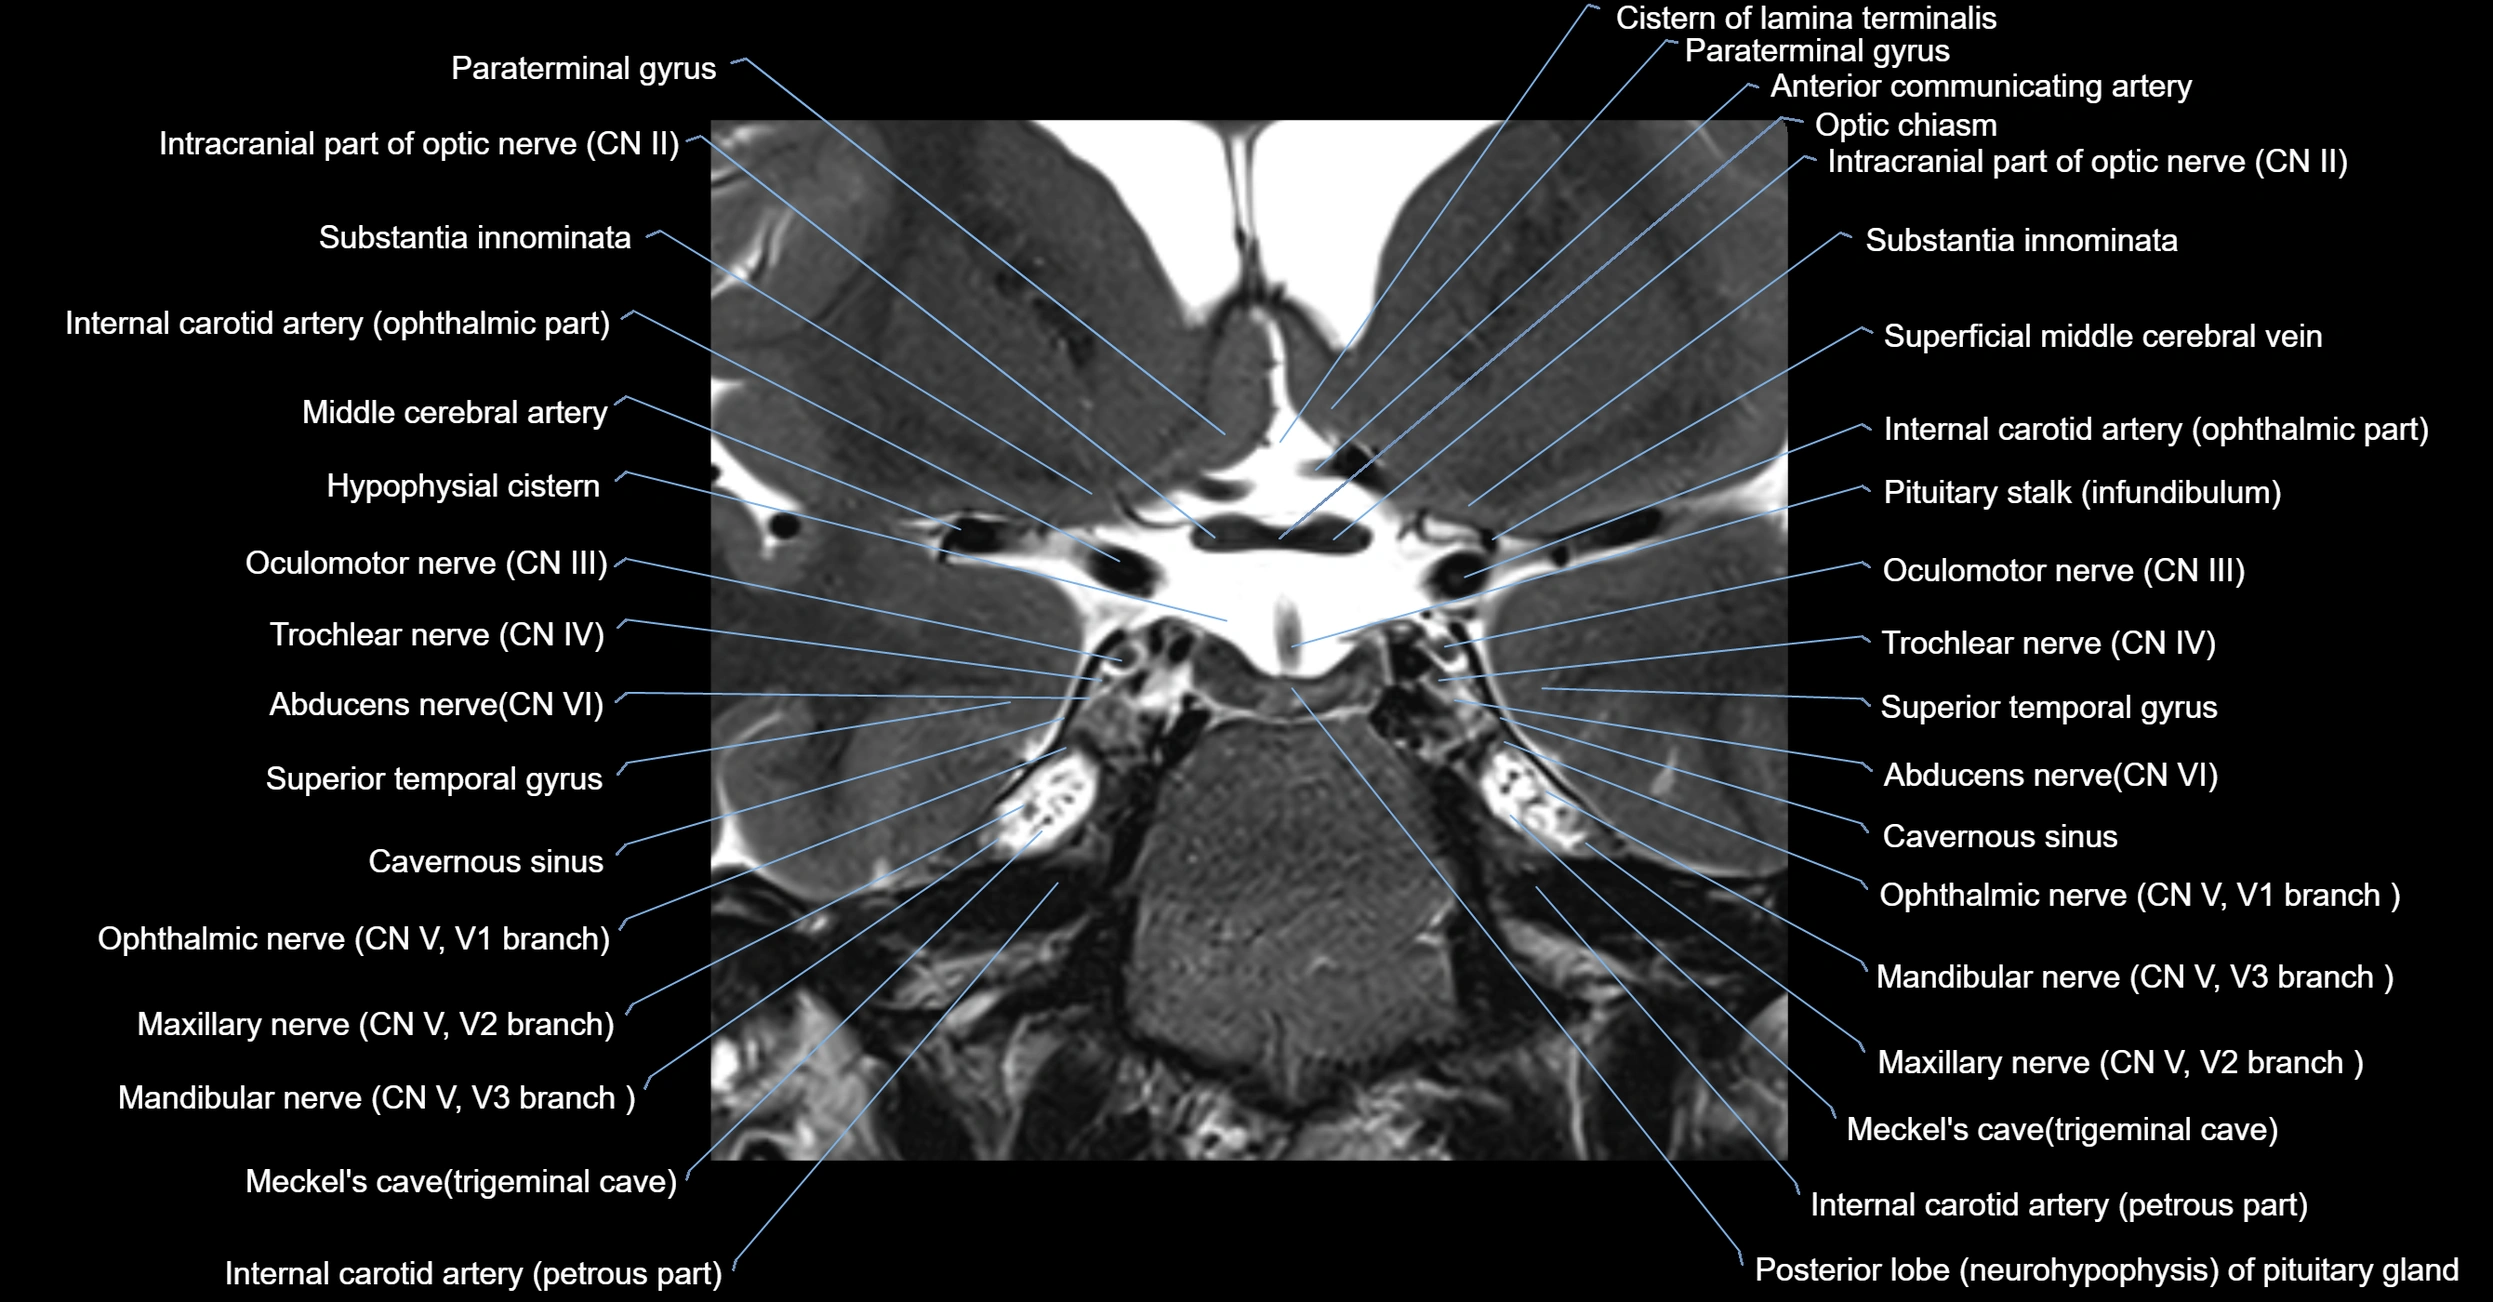

MRI Appearance

The abducens nerve is a small, thin, linear structure

Best visualized on high-resolution T2-weighted 3D MRI sequences (e.g., FIESTA or CISS)

Seen as a hypointense (dark) line running from the brainstem at the pontomedullary junction, traversing the prepontine cistern, and entering Dorello’s canal under the petrosphenoidal ligament, then into the cavernous sinus, and finally the orbit

May be challenging to visualize in standard MRI due to its small size

Pathology may be inferred by absence, displacement, or enhancement of the nerve